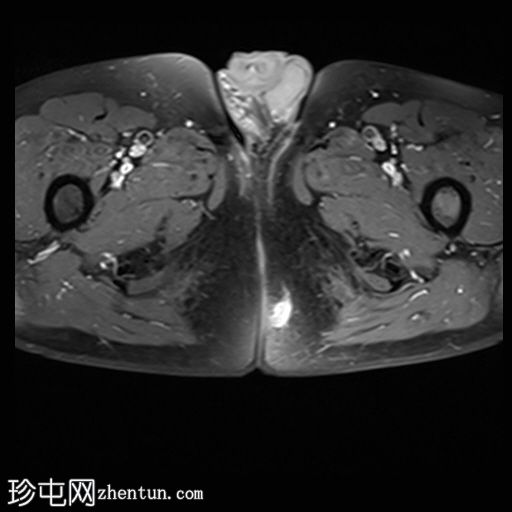

7.jpg

冠状位T1

脂肪饱和度

位于5点钟和6点钟位置之间,在STIR和T2加权图像上呈高信号。

瘘管起源于括约肌间平面附近,穿过肛门内外括约肌,并延伸至左侧坐骨肛门窝。瘘管内充满液体信号,周围有轻微水肿。肛提肌上方未观察到颅骨延伸。

根据圣詹姆斯大学医院的磁共振分类系统,该病例被归类为III级左侧肛周经括约肌瘘,左侧坐骨肛门窝可见炎症改变。